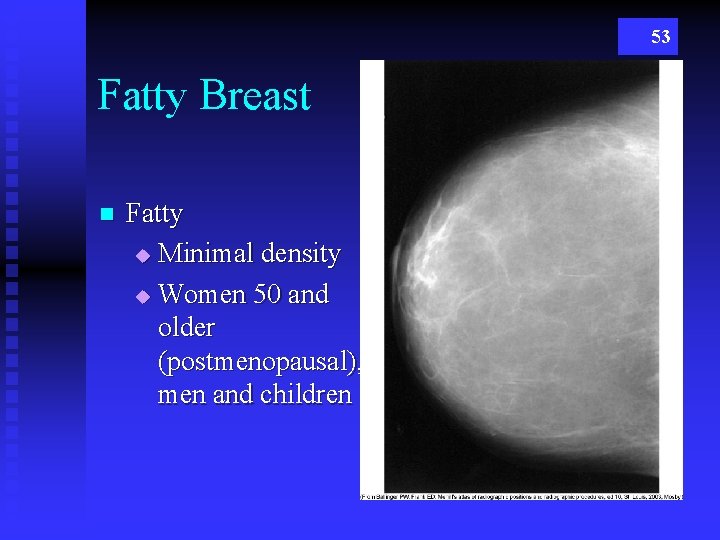

53 Fatty Breast n Fatty u Minimal density u Women 50 and older (postmenopausal), men and children